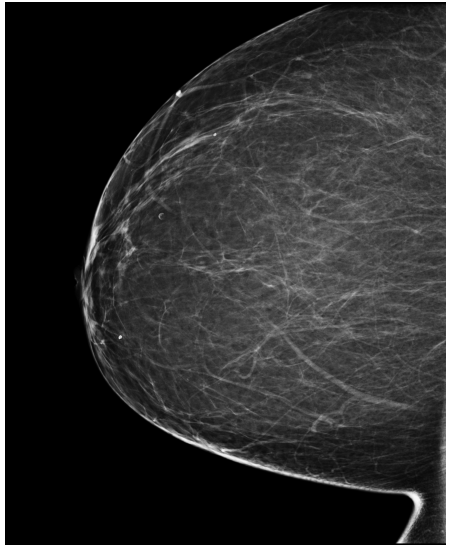

4.3 Pre-processing

The EMBED and CSAW-CC datasets originally consist of images in DICOM format, which are converted into 16-bit grayscale PNG images for consistency and compatibility. Following the pre-processing procedure outlined in (Yala et al.,, 2021), we enhanced image quality and removed background artifacts—such as textual annotations commonly present in mammography images—by applying a contour detection procedure. All contours in the image are detected, and only the largest contour, corresponding to the breast tissue, is retained. This contour is then used to create a mask that isolates the breast region from the background. The isolated breast image is resized to a size of 1664×20481664\times 2048 pixels while preserving the aspect ratio. Finally, the resized image is normalized and converted to a 16-bit format.